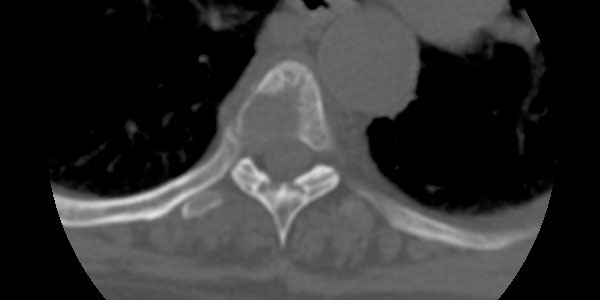

CHONDROSARCOMA

Chondrosarcoma is a malignant tumor of the bone that originates from cartilage tissue. Chondrosarcoma usually occurs after the age of 40 and is more common in men.